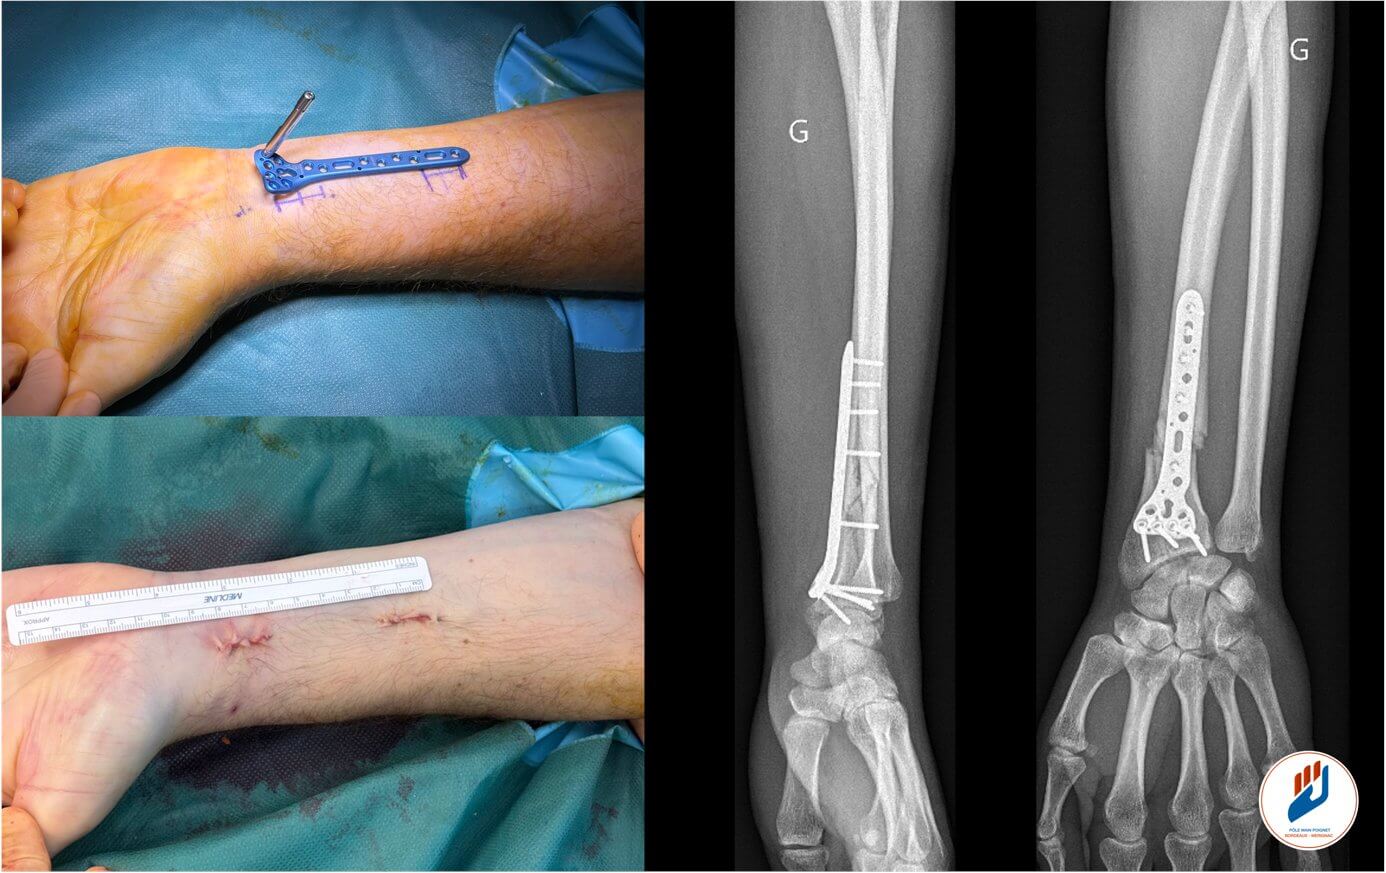

MIPO signifie « Minimally Invasive Plate Osteosynthesis », soit ostéosynthèse par un abord mini-invasive. Il s’agit d’une technique chirurgicale utilisant une plaque palmaire verrouillée, mais posée en utilisant une petite incision (1,5cm) mais surtout en préservant les structure voisine de la fracture : Vascularisation, muscle…

Contrairement à l’abord classique, la technique MIPO ne nécessite pas de grande ouverture. La plaque est insérée sous les tissus (notamment le muscle carré pronateur) et glissée au contact la fracture, ce qui permet :

Comment se déroule l’intervention MIPO ?

L’intervention se déroule généralement en ambulatoire, sous anesthésie loco-régionale ou générale.

- Une incisions de 1,5cm de long est réalisée sur la face palmaire du poignet

- La partie distale du radius est exposée en préservant les structures au contact de l’os, permettant l’introduction de la plaque.

- La fracture est reduite sur la plaque sous contrôle radiographique ou/et arthoscopique en commençant par la partie distale et en finissant par la partie proximale.

- La plaque est fixée avec des vis verrouillées.

- Les incisions sont refermées par un surjet de fils non résorbable.

L’utilisation de vis verrouillées crée un montage extrêmement stable, capable de supporter rapidement les mouvements du poignet.